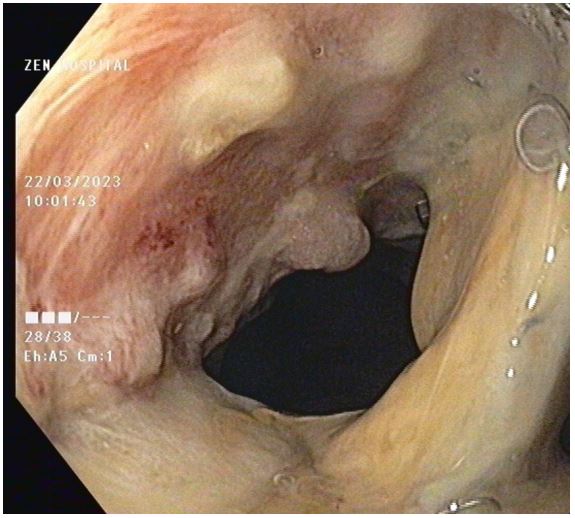

A 31-year-old female patient with a Bochdalek hernia with complete stomach migration into the left pleural space and ischaemia. Intraoperatively, after bringing down the stomach, the proximal half was found to be gangrenous with perforation. Upper partial gastrectomy and esophagogastric anastomosis were performed. The surviving stomach was oedematous and ischemic, but not gangrenous. A CT scan with intravenous contrast 48 hours later revealed a severely ischemic stomach, raising concerns about its viability. A recheck laparotomy to test the stomach remnant revealed considerable edoema but looked viable. The anastomotic site looks healthy. On the 12th postoperative day, an oral contrast study revealed a frank leak from the anastomosis, with the infected collection tracking up to the left perinephric space, with endoscopy confirming the results (Figure 6). At this point, management options were limited. The covered stent and reoperation were deemed risky. Endoscopic Vacuum (E-VAC) therapy was considered a safe choice in these conditions.

A UGI endoscopy performed to prepare for the endovac revealed a partial breakdown of the anastomosis with a defect size of 3 cm and a subdiaphragmatic cavity filled with slough. The cavity was entered with a scope, and de-sloughing was accomplished with a brush. Normal saline was used to irrigate the cavity. Endovac was used. Forty-eight hours after beginning endovac therapy, there was a significant decrease in SIRS response as measured by fever, pulse rate, WBC count, and CRP. Endovac was done twice more at 5-day intervals. The therapy lasted two weeks in total. At each endoscopic session, the size of the sponge used was reduced, and the cavity size and amount of slough were significantly improved (Figure 7). After 2 weeks of endovac therapy, a CT oral contrast study revealed a significant reduction in cavity size with a well-formed fistula that closed in about 8 weeks. Endoscopies were performed at 3 and 6 months. Both were normal, and the patient is currently on a complete oral diet.

Figure 6: Post operative anastamotic site leak in stomach and placement of E Vac sponge.

Figure 7: Healed anastamotic leak of stomach after E vac therapy.